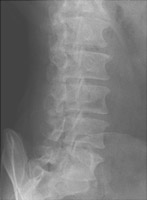

- Click on the image for a larger versionCConed radiograph of the L5-S1 region. The abnormalities are difficult to appreciate.